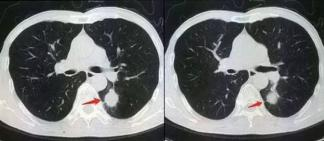

图 1 肺结节 CT 图像

Fig.1 CT images of pulmonary nodules

教师应当充分考虑科研水平和力度,为大学生创新 发展提供相应的保障和支撑,医学图像处理教学改革在 人工智能技术的保障下更加先进科学,就以肺结节 CT 图像为例(如图 1)。该系统已经获得明确授权,并赢 得多个奖项。肺结节计算机辅助系统包括医学图像处理的基本理论和体系,在具体分类时需要运用人工智能手 段进行补充和完善,为医学图像处理提供更多便利条件。